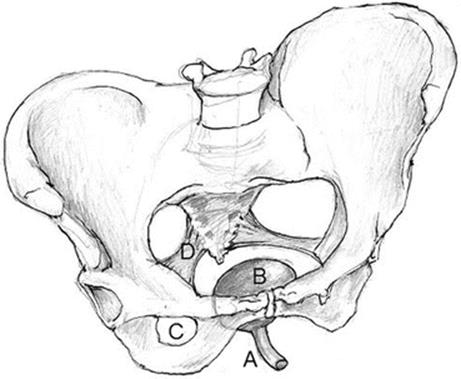

The goal of female pelvic reconstructive surgical procedures is to take advantage of the bony pelvis, relevant pelvic ligaments, and muscles to restore normal anatomy. These structures are reviewed briefly in the context of a survey of common urogynecological procedures (Fig. 19.1).

Fig. 19.1

Female pelvic anatomy . (A) Urethra, (B) bladder, (C) obturator foramen, (D) sacrospinous ligament